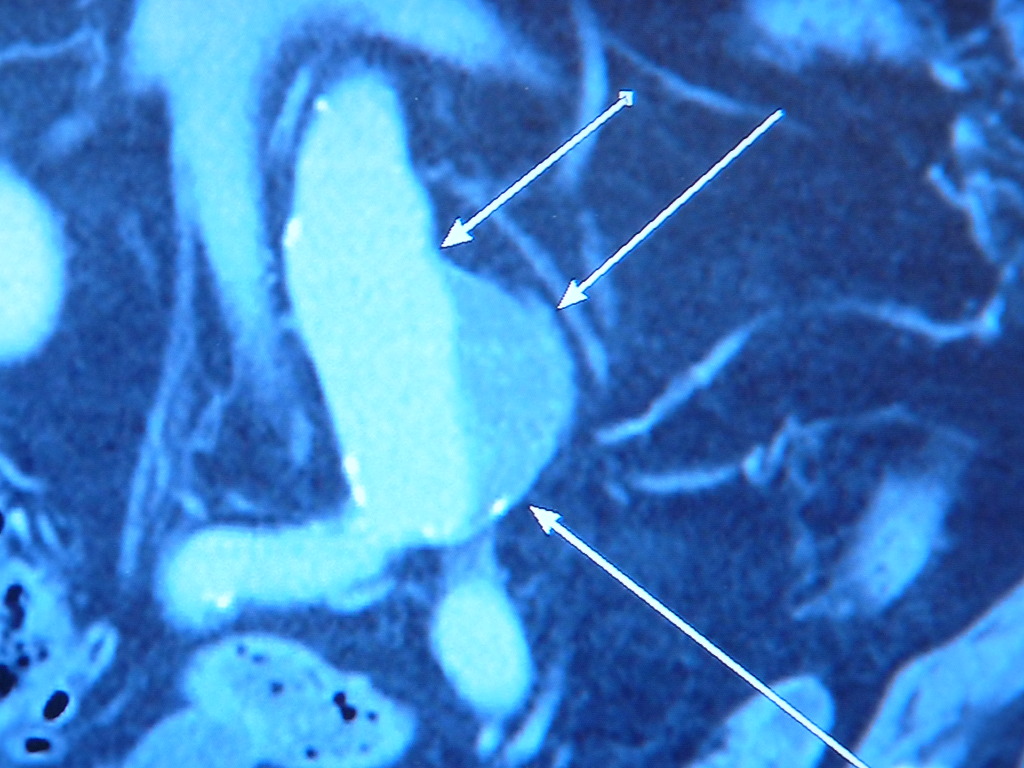

동맥류는 동맥이 있는 곳은 어디든지 발생할 수 있지만 뇌동맥류와 복부동맥류에서 가장 많이 발생한다. 그외에도 신장동맥류, 슬동맥류, 쇄골동맥류 등에서도 발생하고 있다.